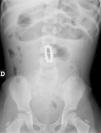

Niña de 2 años y 10 meses de edad traída a Urgencias por vómitos alimentarios incoercibles de 2 días de evolución, estreñimiento y dolor abdominal continuo en el hemiabdomen derecho. Los padres no conocían la ingesta de ningún cuerpo extraño. En la exploración se encuentra afebril, decaída, con regular estado general y signos clínicos de deshidratación. El abdomen está distendido y timpánico, doloroso a la palpación profunda difusa, sin signos de peritonismo y ruidos hidroaéreos disminuidos. En la radiografía de abdomen (fig. 1) se confirman los signos de obstrucción abdominal y la presencia de un objeto radioopaco «en forma de cuentas» a nivel del yeyuno. Tras interconsulta al Servicio de Cirugía, se decide intervención urgente. Durante la cirugía se confirma la existencia de una pulsera de imanes, dividida en 2 porciones, que ha provocado la adhesión entre 2 asas del intestino delgado y la formación de un vólvulo intestinal, con la consecuente obstrucción mecánica (fig. 2). Tras la resección de 2 segmentos intestinales adheridos de 5cm de longitud y la extracción del objeto magnético, se realizó una anastomosis término-terminal yeyunal e ileal a 130cm y 60cm de la válvula ileocecal, respectivamente. Respecto a los factores que pueden contribuir al retraso en el diagnóstico, hay que destacar 2 aspectos. En primer lugar, es habitual que los padres desconozcan el antecedente de cualquier ingesta de cuerpo extraño, unido a la actitud reticente de los niños a admitirla. Por otro lado, a pesar de las graves complicaciones intestinales, los pacientes pueden presentarse con escasos síntomas no específicos y relativamente pocos hallazgos físicos y de laboratorio.